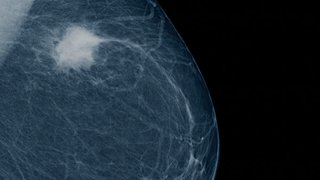

Enhancing Immunotherapy Drug Trials for Patients with Breast Cancer

- Sangeetha Reddy, M.D.

July 27, 2020